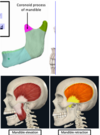

what muscle is this? where is it? where does it insert? innervated by..? function?

Temporalis *Fan-shaped muscle * Lies within the temporal fossa of the temporal bone * Its tendon inserts on the coronoid process of the mandible Actions: *Elevates the mandible *Retraction of mandible

62

what is this muscle? function? originates? inserts? innervation?

Masseter * Masseter= “chewer” * Originates from the zygomatic arch and zygomatic bone * Its tendon inserts on the ramus and angle of the mandible * It has 2 heads: * Superficial head * Deep head